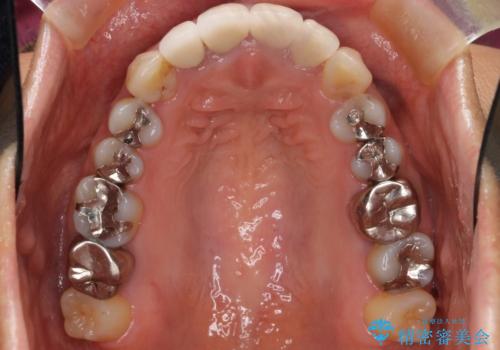

- 奥歯に違和感があることを主訴に来院された患者様です。

精査したところ、右上の奥歯(右上7)はう蝕が深く骨吸収も進行しており保存不可能な状態でした。

クラウンの種類:オールセラミッククラウン ベレッツァ